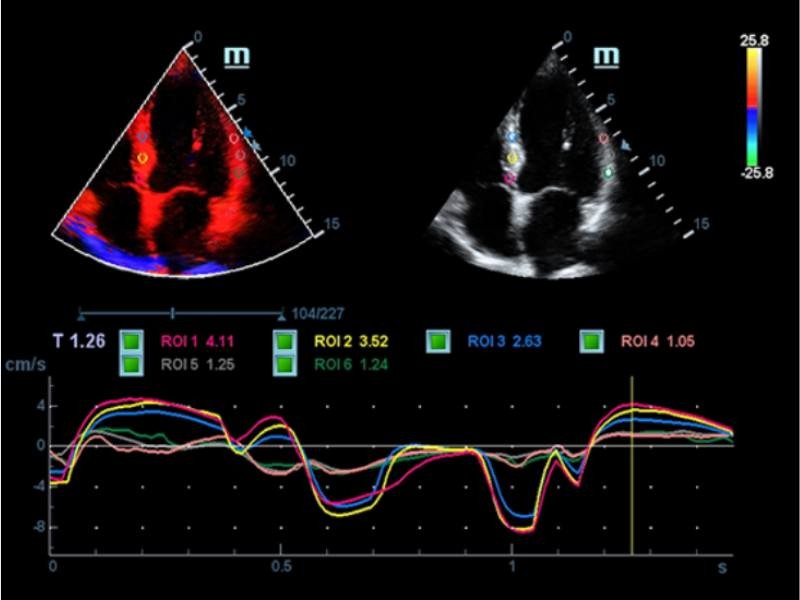

EF automático

A Auto EF é uma forma inteligente de analisar clipes de eco 2D para reconhecimento automático de quadros de diástole/sístole e os resultados de uma série de medidas para avaliar a função do ventrículo esquerdo para maior produtividade, tais como EDV/ESV/EF.